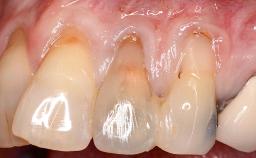

Treatment of Soft-Tissue Fenestration in the Esthetic Zone

This case demonstrates that a connective-tissue graft in combination with a coronally positioned graft is an effective method of treating cases with peri-implant mucositis and an abutment-level sinus abscess. A 42-year-old man presented with a swelling adjacent to an implant crown at site 21. The swelling had been present for approximately three weeks and was constrained to the buccal and palatal gingival aspects of the implant. A discharge was noted on finger pressure, with localized gingival recession present on the mid- and distolabial aspects of the crown.